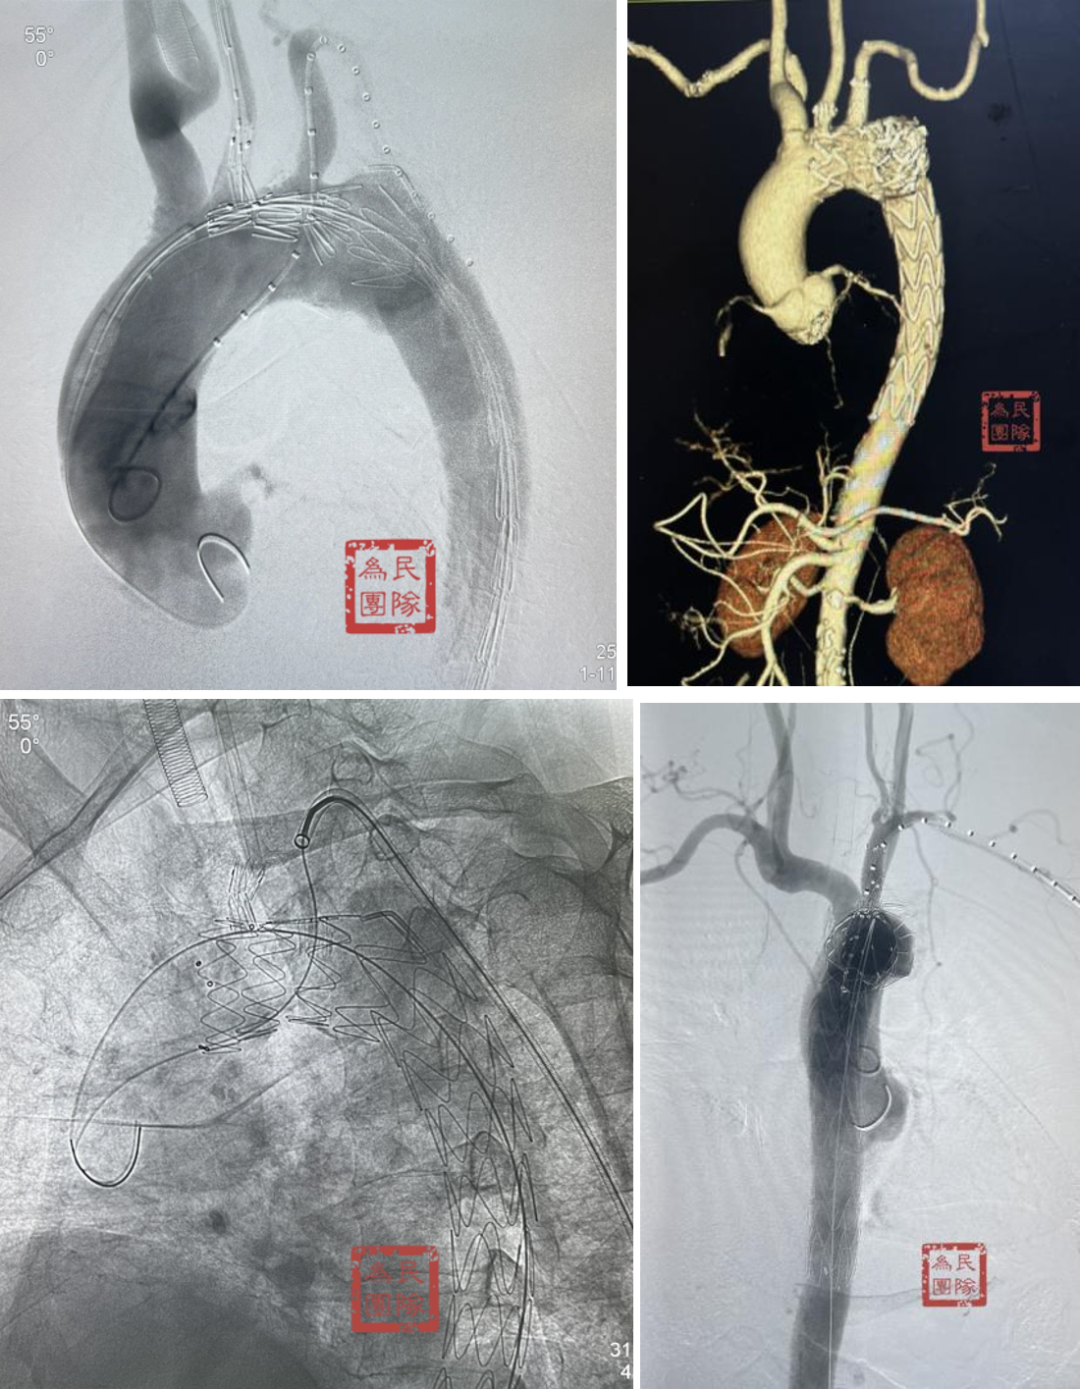

【原位三开窗技术】紧急情况的有效选择

原位三开窗技术是指在主体支架释放后,通过穿刺或烧灼在支架覆膜上开窗,重建分支血管血运的技术。

典型病例:一例TEVAR术后三个月发现内漏的患者,采用原位三开窗技术,依次开通左颈总动脉、头臂干、左锁骨下动脉。在有效脑保护下完成操作,术后七年随访效果理想。

另一例逆撕至头臂干的A型夹层患者,在ECMO辅助下行原位三开窗,术中虽出现心跳骤停,但通过ECMO模式转换成功救治,随访六七年CT显示良好。

【体外预三开窗】精准规划的选择

体外预开窗技术是根据术前测量结果,在支架上预留对应分支开口,支架释放后开口对准分支开口以保留分支血供。

技术改进:通过3D打印模型辅助术中操作,先对准左颈总动脉,再对准左锁骨下动脉,用球囊扩张固定后再释放支架,为纠错和防止移位争取时间。

复杂病例应用:巨大弓部动脉瘤(5.5cm)且左锁骨下动脉位于瘤腔内:在预开窗基础上加做左锁骨下动脉内嵌分支,配合3D打印模型辅助和束径技术,术后随访效果理想

A型夹层合并迷走左椎动脉:针对头臂干、左颈总和左锁骨下动脉进行预开窗,对非优势且纤细的迷走左椎动脉仅作小洞处理,术中对位良好